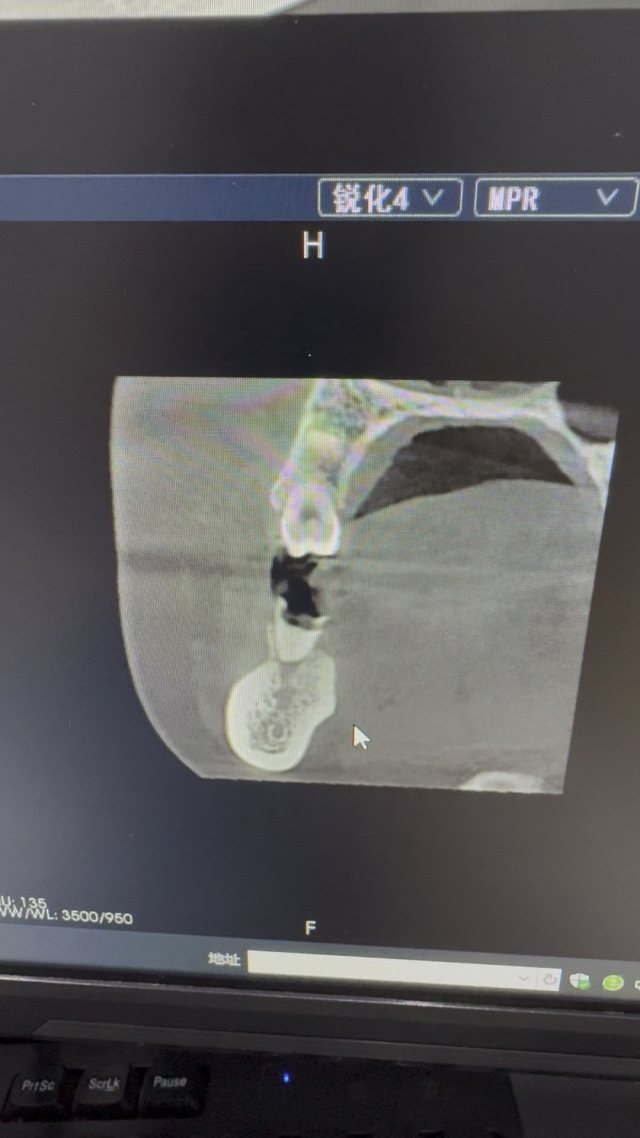

西地兰vip普外科医师

文/西地兰 特别声明:所有观点仅代表个人言论 特别声明:与当事双方均无利益相关 山东男孩,目前全网沸沸扬扬,看过一些观点,直言不讳地说,大多偏颇。要么一股脑地指责医方的全责,甚至有说千万别在县医院看病。要么又为医方无休止的遮羞,认为这样的手术在县医院做下来已经非常了不起。而我想到的是,以后面临类似的病例,我们怎么办?那么我们不如来一次专业的病案讨论。既然是事后讨论,难免有事后诸葛亮的感觉,但是假如下一次,同行们遭遇这样的病例,如何处置?这是医疗行业所面临的问题。希望我整理的这些思路和相关病例,对同行们有所帮助!就目前的资讯外界不足以判断是否需要急诊,如果需要急诊,那么只能根据术中所见进行处理,

目前知道的消息,第一,术前发现一个血肿,然后做增强CT发现一个占位,没说血肿与肿瘤的关系,术后病理没有描述肿瘤出现破裂出血,大概率就一个小血肿,我就不明白当地主任凭哪个指针去给这小孩开急诊刀的?哪个指南告诉他需要急诊开?第二,诊断不明确他想的不是进一步检查,一边观察一边进一步查,他反而选择腹腔镜探查,这个探查的指针在哪?第三,腹腔一个血肿,没有活动性出血,没有血压心率出现问题,为什么要开腹进去碰它?不能等血肿吸收再明确肿瘤性质吗?第四,1点进腹,3点病理结果出来,按这个时间还算顺利,应该还没出事,孩子还算平稳,病理是低度恶性,切了就治愈,他一年能开几台这手术,就敢继续做,拿孩子练手。第五,后面

2023年10月26日,来自山东菏泽市成武县的小烨和他家人的命运被彻底改变了。这个原本阳光、可爱的小男孩在一次意外被撞击后,在医院检查出了腹腔内存在肿瘤,并在手术中被切除了包括十二指肠、胰腺、大部分胃和小肠等多个器官。此后便无法再像正常人一样吃饭、喝水,活着要靠长期静脉注射营养液。一份2024年12月由第三方机构出具的司法鉴定意见书显示,当时给小烨做手术的成武县人民医院在该医疗行为中存在过错,与小烨的损害后果之间存在因果关系,建议医疗过错在损害后果中的原因力大小为同等原因。此外,另一份由成武县卫生健康局在2025年9月28日发出的书面答复中显示,成武县人民医院存在24小时内未完成病历;手术知情